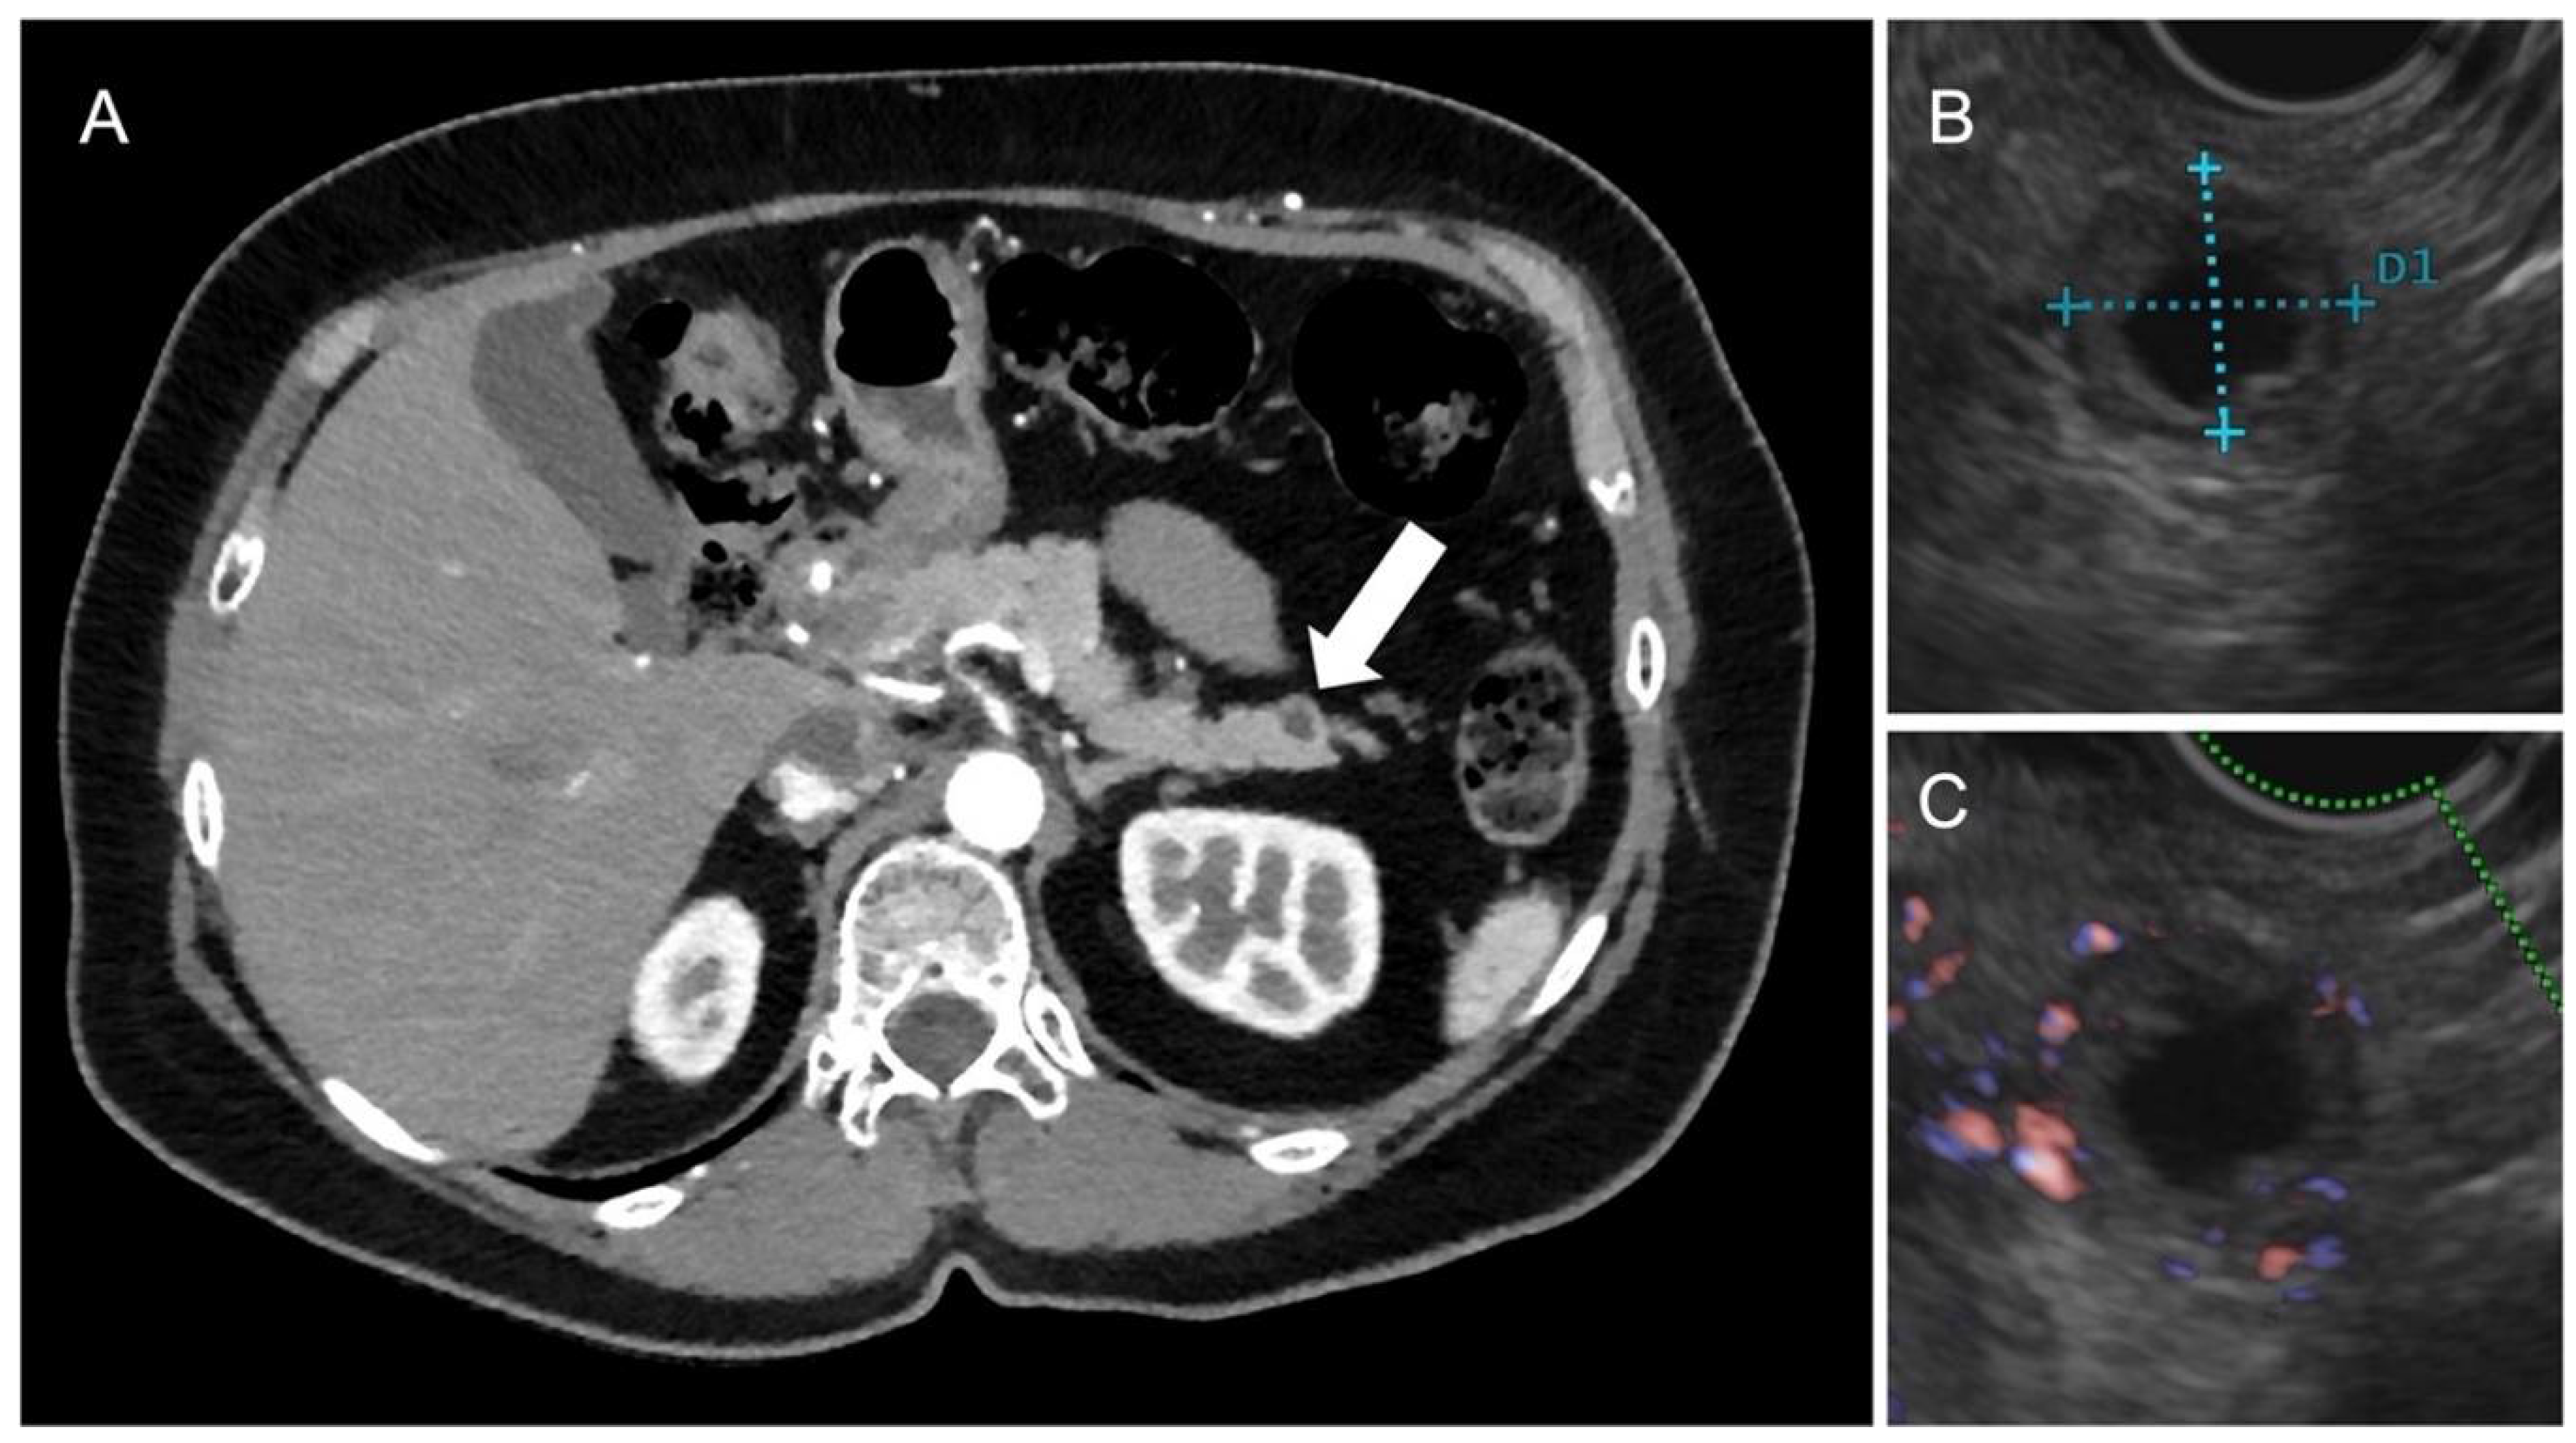

- Ciaravino, V.; De Robertis, R.; Martini, P.T.; Cardobi, N.; Cingarlini, S.; Amodio, A.; Landoni, L.; Capelli, P.; D’Onofrio, M. Imaging presentation of pancreatic neuroendocrine neoplasms. Insights Imag. 2018, 9, 943. [Google Scholar] [CrossRef] [PubMed]

- Ichikawa, T.; Peterson, M.; Federle, M.; Baron, R.; Haradome, H.; Kawamori, Y.; Nawano, S.; Araki, T. Islet cell tumor of the pancreas: Biphasic CT versus MR imaging in tumor detection. Radiology 2000, 216, 163–171. [Google Scholar] [CrossRef] [PubMed]

- Sundin, A.; Vullierme, M.; Kaltsas, G.; Plöckinger, U.; Åkerström, G.; Annibale, B.; Arnold, R.; Bajetta, E.; Barkmanova, J.; Chen, Y.; et al. ENETS Consensus Guidelines for the Standards of Care in Neuroendocrine Tumors: Radiological examinations. Neuroendocrinology 2009, 90, 167–183. [Google Scholar] [CrossRef] [PubMed]